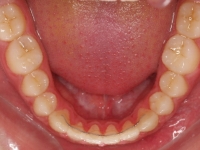

El stripping consiste en la reducción interproximal del esmalte entre los dientes posteriores y anteriores, así obtenemos espacio para alinear los dientes apiñados.

Chica de 17 años tratada en 1 año con stripping en los dientes inferiores